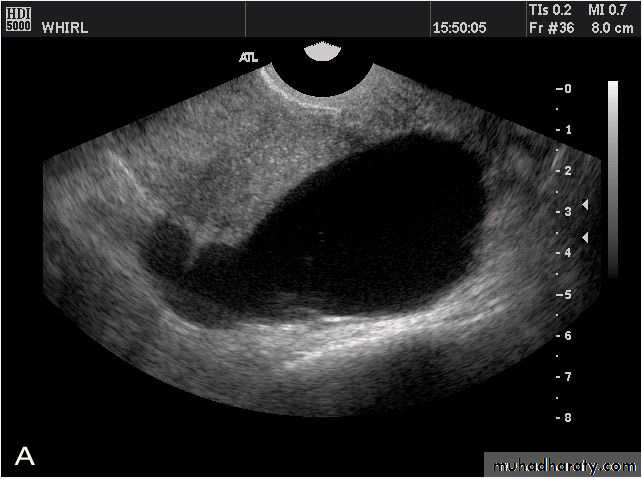

This young female patient underwent sonography for non-specific pain in the lower abdomen. Ultrasound images of the pelvis show bilateral ovarian cysts which show absence of internal nodules, septae or debris. These findings are typical of follicular cysts of the ovaries. Follicular cysts are functional cysts and are enlarged ovarian follicles that have not ruptured (ovulated). They are usually unilateral.